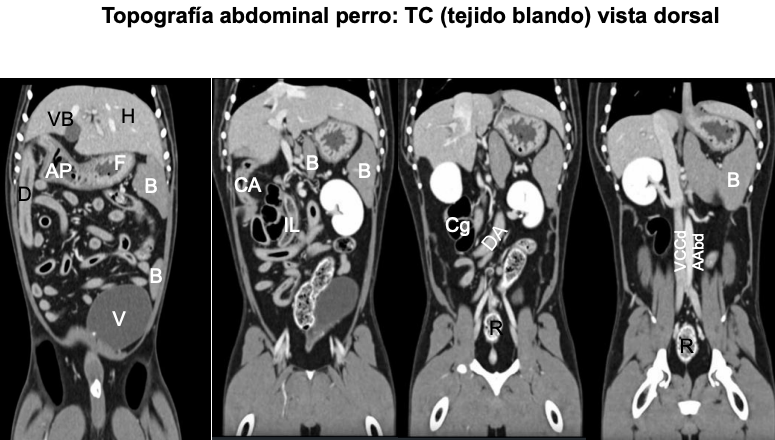

Topogradía abdominal del perro: Tac o TC del tejid blando, vista dorsal

Generalmente las imagenes de tac están espejadas

En gato el bazo siempre esta en la izquierda, el perros la cola puede estar a la derecha

IMAIOS para repasar imagenes de tac